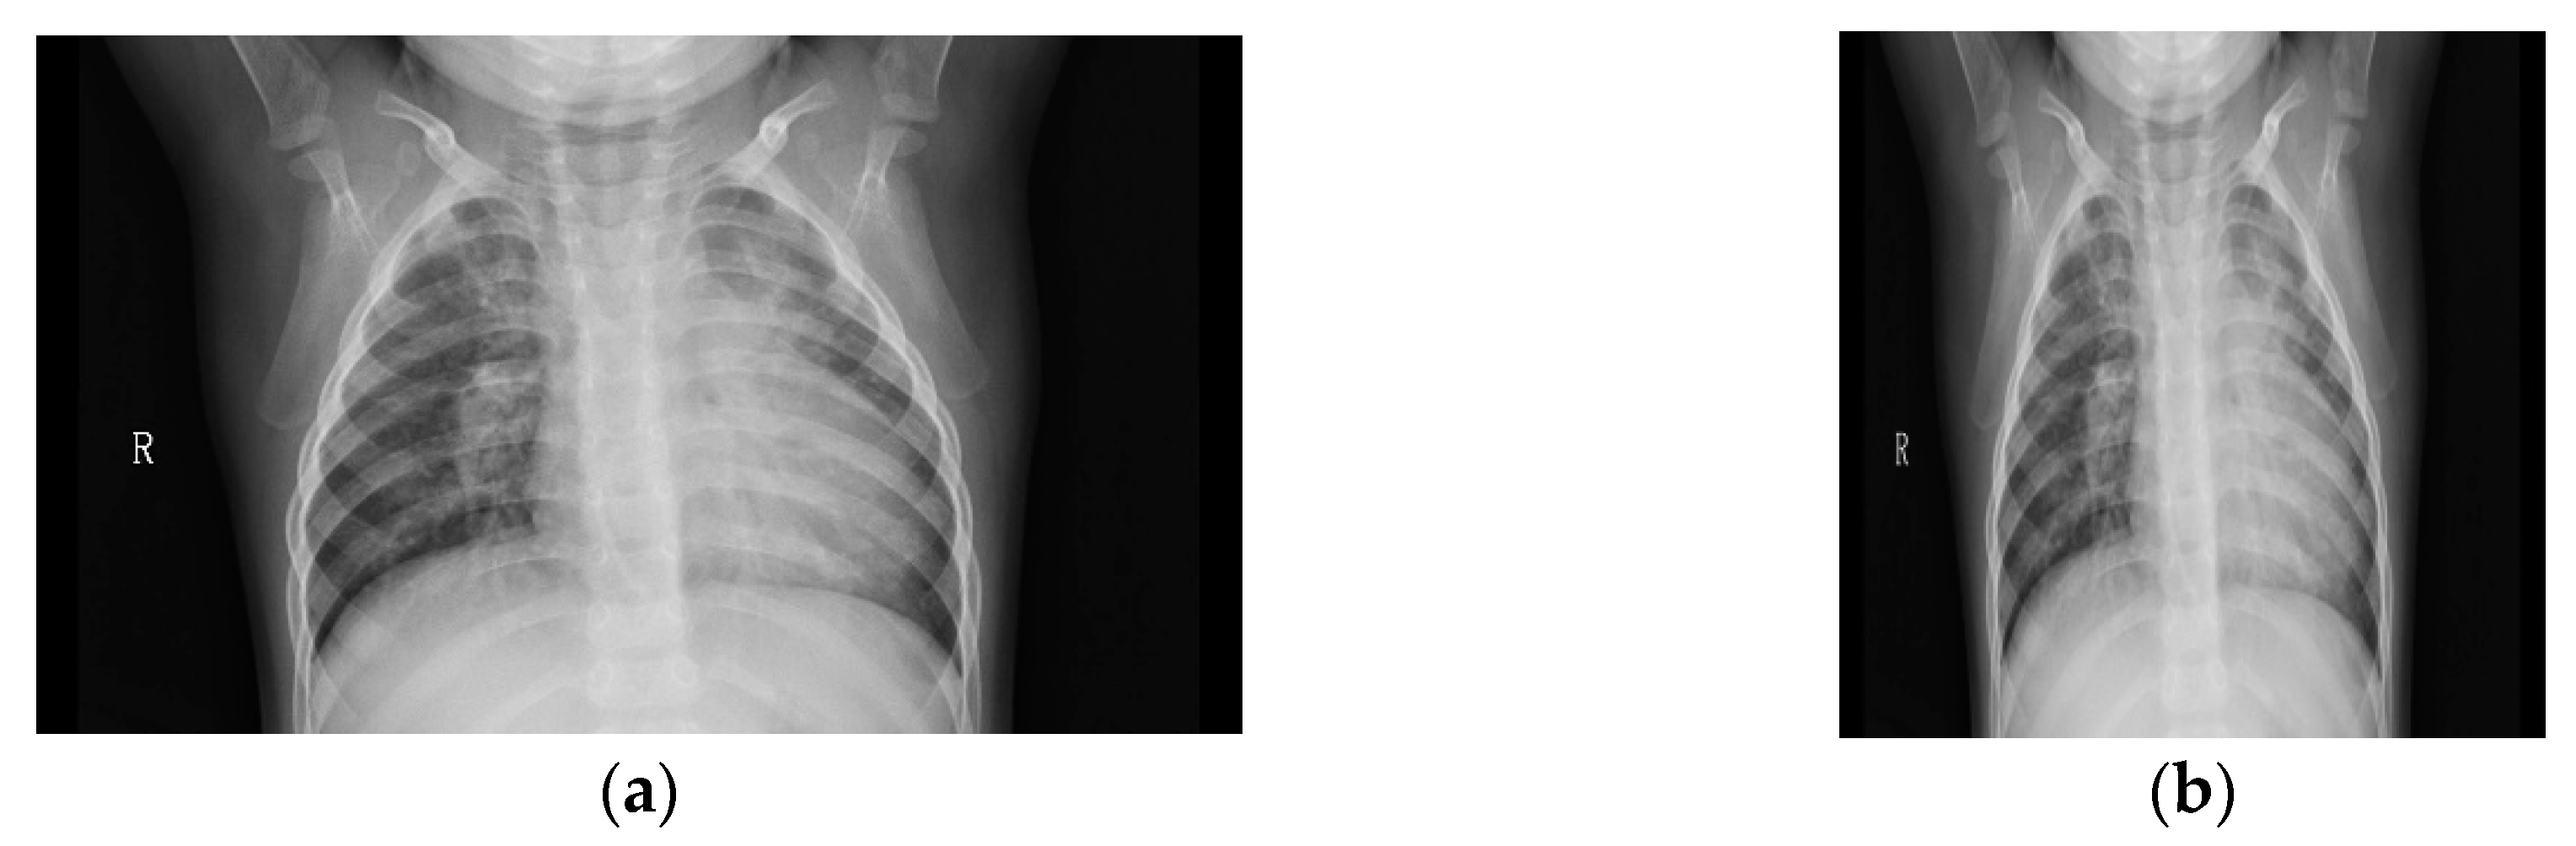

3.1. Pneumonia Dataset

4.1. Image Preprocessing

- Remove any possible black band from the edges of the image.

- Resize the image to achieve that the smaller edge is (in our case) 299 pixels long.

- Extract the central 299 × 299 region.